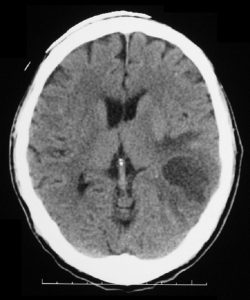

Jedná se o zařízení pracující s rentgenovým zářením podobně jako běžný RTG přístroj, u CT (computed tomography) však rotuje zdroj záření – rentgenka i detekční systém okolo těla pacienta, který je tak ozařován postupně z různých úhlů po celém obvodu těla. Detekční systém pak vyhodnocuje množství záření procházející tělem pacienta pod různými úhly a z těchto dat jsou následně pomocí výkonného počítače zrekonstruovány jednotlivé scany – obrazy vrstev těla zpravidla v axiální rovině.

U klasického RTG snímku je výsledkem sumační obraz z celého těla, na kterém se stíny jednotlivých struktur překrývají; u CT vyšetření získáme tenké vrstvy z vyšetřované oblasti, bez překrývání jednotlivých částí těla, lze tedy zobrazit mnohem přesněji jednotlivé orgány, jejich strukturu a patologické stavy.

Indikace k vyšetření

Vzhledem k relativně velké zátěži rtg zářením je CT indikováno jako „metoda druhé volby“ – doplňující vyšetření, které by mělo pomoci objasnit nejasný nález ultrazvukového vyšetření nebo klasického rtg snímku a to především u posuzování kostí, plic a střev, kde ultrazvukové vyšetření nelze uplatnit. U akutních (neodkladných) indikací používáme CT především pro zobrazování hlavy – mozku při cévních mozkových příhodách a úrazech hlavy, protože velmi dobře zobrazí nitrolební krvácení. Velmi spolehlivě zobrazí i traumatické změny orgánů hrudníku, břicha, pánve i zlomeniny kostí. Další velmi důležitou akutní indikací CT vyšetření je podezření na postižení aorty (srdečnice), jako je výduť nebo dissekce (odtržení výstelky) aorty. V daném případě se provádí CT angiografie (vyšetření cév pomocí CT), hlavně pro zobrazení velkých tepen (aorty, renální tepny, pánevní tepny, karotidy) a také pro zobrazení mozkových tepen (circulus arteriosus Willisi). V některých případech může zcela nahradit klasické angiografické vyšetření.

Přístrojové vybavení a ukázkové snímky:

- CT Siemens SOMATOM DEFINITION AS+ 128CT přístroj Somatom Definition AS+ značky Siemens umožňuje současné snímání 128 vrstev na jednu otočku rentgenky. Výjimečné prostorové rozlišení nabízí zobrazení tkáňových struktur od velikosti 0,24 mm, rozsah snímání obrazu 200 cm v kombinaci s tímto rozlišením zase umožňuje vyšetření celého těla pacienta během 10 vteřin. To je obzvlášť důležité při vyšetření pacientů s těžkými úrazy, v bezvědomí nebo u nespolupracujících pacientů. Tyto výjimečné parametry jsou využitelné zejména v traumatologii, kdy se jedná o co nejrychlejší stanovení diagnózy, a v kardiologii, kde umožňují vyšetření funkce srdce a hodnocení koronárních tepen včetně analýzy kalcifikací v jejich stěnách.Rychlost a kvalita obrazů je výhodná pro kvalitativní vaskulární diagnostiku a plánování intervenčních zákroků na cévách. Plně automatická funkce objemového zobrazení (3D) usnadňuje vyhodnocení prokrvení mozku. Snímky z tohoto přístroje jsou generovány ve formátu DICOM, což umožňuje jejich okamžité předání do systému PACS a prohlížení odeslaných CT obrazů na klinických pracovištích.